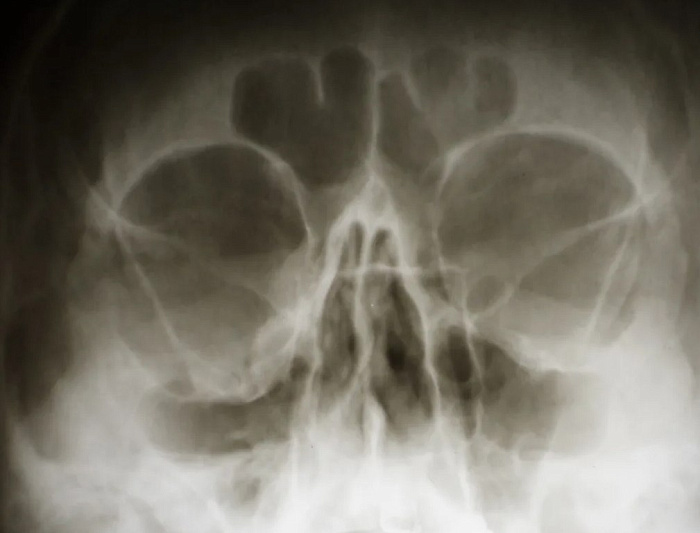

Рентгенография глазницы – важный метод прицельного исследования, который позволяет оценить целостность скуловой кости. Диагностическая услуга выполняется в одной/двух проекциях.

• подозрение на перелом глазницы;

• воспалительные процессы в области глаз.